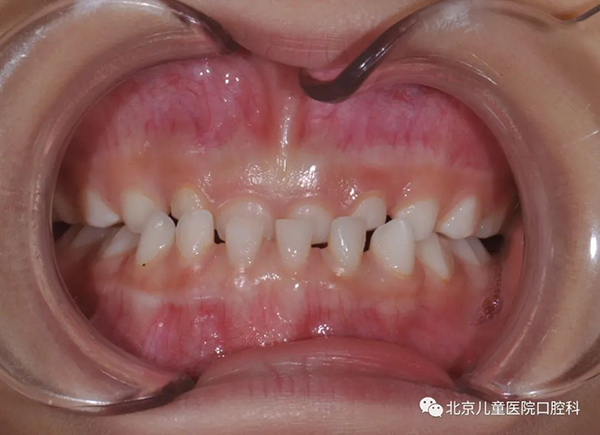

咬下唇导致上前牙唇倾,出现间隙

② 咬上唇习惯:比较少见。通常患者下颌向前把上唇咬在下前牙和上前牙之间,上唇肌肉压迫上前牙,使其向内倒,出现拥挤,同时使下前牙向前突出,出现散在间隙,甚至形成兜齿或下颌前突。